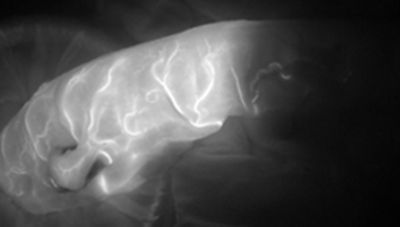

SPY Portable Handheld Imager (SPY-PHI) utilizes SPY Fluorescence Imaging technology and is designed to allow surgeons to visualize blood flow in vessels and related tissue perfusion during plastic, microsurgical, reconstructive and gastrointestinal procedures.

Upon intravenous administration of SPY AGENT GREEN (indocyanine green for injection, USP), the SPY-PHI System is used with SPY AGENT GREEN to perform intraoperative fluorescence angiography. The SPY-PHI System is indicated for use in adult and pediatric patients one month of age and older. The SPY-PHI System is indicated for fluorescence imaging of blood flow and tissue perfusion before, during, and after: vascular, gastrointestinal, organ transplant, and plastic, micro- and reconstructive surgical procedures. Upon interstitial administration of SPY AGENT GREEN, the SPY-PHI System is used to perform intraoperative fluorescence imaging and visualization of the lymphatic system, including lymphatic vessels and lymph nodes. Upon intradermal administration of SPY AGENT GREEN, the SPY-PHI System is indicated for fluorescence imaging of lymph nodes and delineation of lymphatic vessels during lymphatic mapping in adults with breast cancer for which this procedure is a component of intraoperative management.